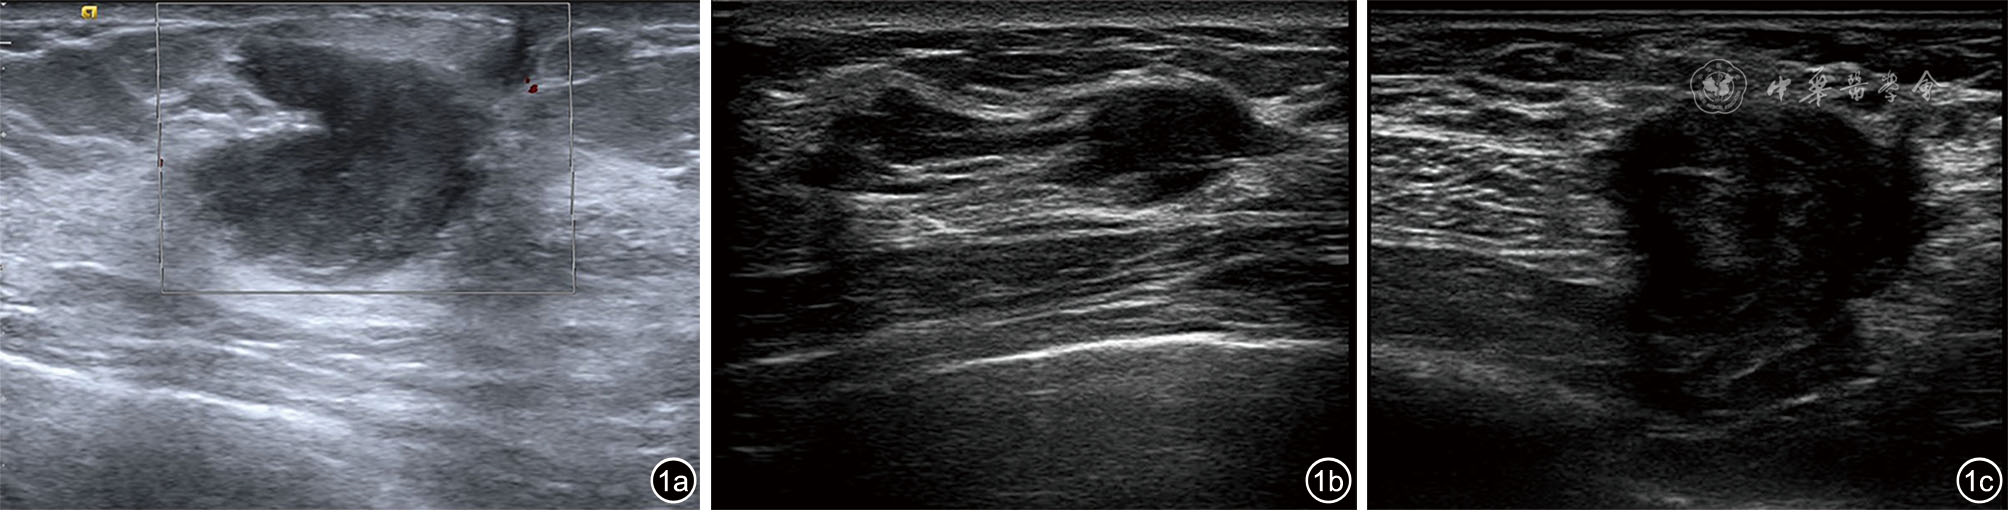

Kyoung JH, Eun-Kyung K, Hee KK, et al. Breast fibromatosis showing unusual sonographic features [J]. J Ultrasound Med, 2010, 29(11): 1671-1674.

董叶, 彭晓静, 邓晶, 等. 高频超声诊断侵袭性纤维瘤病的应用价值 [J]. 临床超声医学杂志, 2021, 23(1): 69-72.

宗晴晴, 邓晶, 许迪. 乳腺纤维瘤病超声表现与病理结果对照研究及误诊分析 [J]. 肿瘤影像学, 2019, 28(6): 384-389.